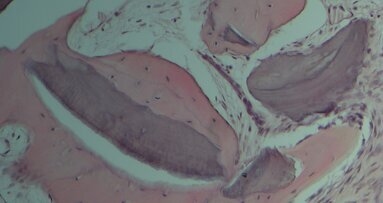

L’analisi istologica è stata effettuata sui campioni prelevati a 3 mesi dall’intervento di preservazione di cresta in entrambi i gruppi sperimentali. Sono stati esaminati la presenza di osso neoformato, di particelle di biomateriale residue e l’interfaccia tra nuovo osso e innesto. In tutte le biopsie, nella zona dell’innesto osseo è stata notata la formazione di osso trabecolare e la presenza di particelle di biomateriale residuo.

Nel gruppo test, i campioni osservati a basso ingrandimento (12X) apparivano formati interamente da osso neoformato e da biomateriale residuo. A ingrandimento maggiore (40X) è stato osservato che i granuli di biomateriale avevano dimensioni variabili. Particelle di piccola dimensione, parzialmente inglobate nell’area di rigenerazione ossea, sono state trovate in alcune zone del campione, mentre in altre sono state reperite particelle di dimensioni maggiori. Al’interno delle particelle e attorno alle stesse è stato notato osso neoformato. Le particelle di materiale innestato presentavano margini irregolari a causa del processo di riassorbimento cui erano soggette. In molte sezioni sono state trovate cellule ossee all’interno dei pori delle particelle. A ingrandimento ancora maggiore (100X), non sono stati rinvenuti gap all’interfaccia tra nuovo osso e biomateriale, e il nuovo osso era in stretto contatto con i granuli. L’osso neoformato, disposto a formare ponti tra le particelle di biomateriale, era caratterizzato da lacune osteocitiche di grosse dimensioni. Il materiale innestato appariva parzialmente riassorbito e sostituito da nuovo osso (Fig. 2). Gli spazi midollari dell’osso neoformato contenevano un numero limitato di cellule stromali midollari e una rete vascolare. Alcuni vasi sanguigni sono stati osservati anche all’interno delle particelle innestate. Non è stata trovata alcuna cellula infiammatoria o cellule di reazione da corpo estraneo sulla superficie del biomateriale.

Nei campioni del gruppo controllo è stata osservata la presenza di tessuto osseo nativo, caratterizzato da zone di rimodellamento che presentavano linee cementizie e osso neoformato in stretto contatto con le particelle di biomateriale. A maggiore ingrandimento (40X) la maggior parte del biomateriale si presentava connesso al nuovo osso e circondato da grosse lacune osteocitiche. I granuli erano parzialmente riassorbiti e sostituiti da nuovo osso. L’osso neoformato è stato osservato anche all’interno delle particelle di biomateriale parzialmente riassorbite.L’osso neoformato presentava alta affinità per i coloranti ed era positivo alla fucsina acida, infatti all’interfaccia tra nuovo osso e biomateriale una linea densamente colorata è stata osservata. A ingrandimento ancora maggiore (100X), sono state osservate lacune osteocitiche di grandi dimensioni. Non sono stati osservati gap all’interfaccia tra osso e particelle, e l’osso neoformato era sempre in stretto contatto con il materiale innestato. All’interno degli spazi midollari sono state osservate cellule stromali midollari e vasi sanguigni (Fig. 3). Una neovascolarizzazione è stata notata anche attorno ai granuli dell’innesto.